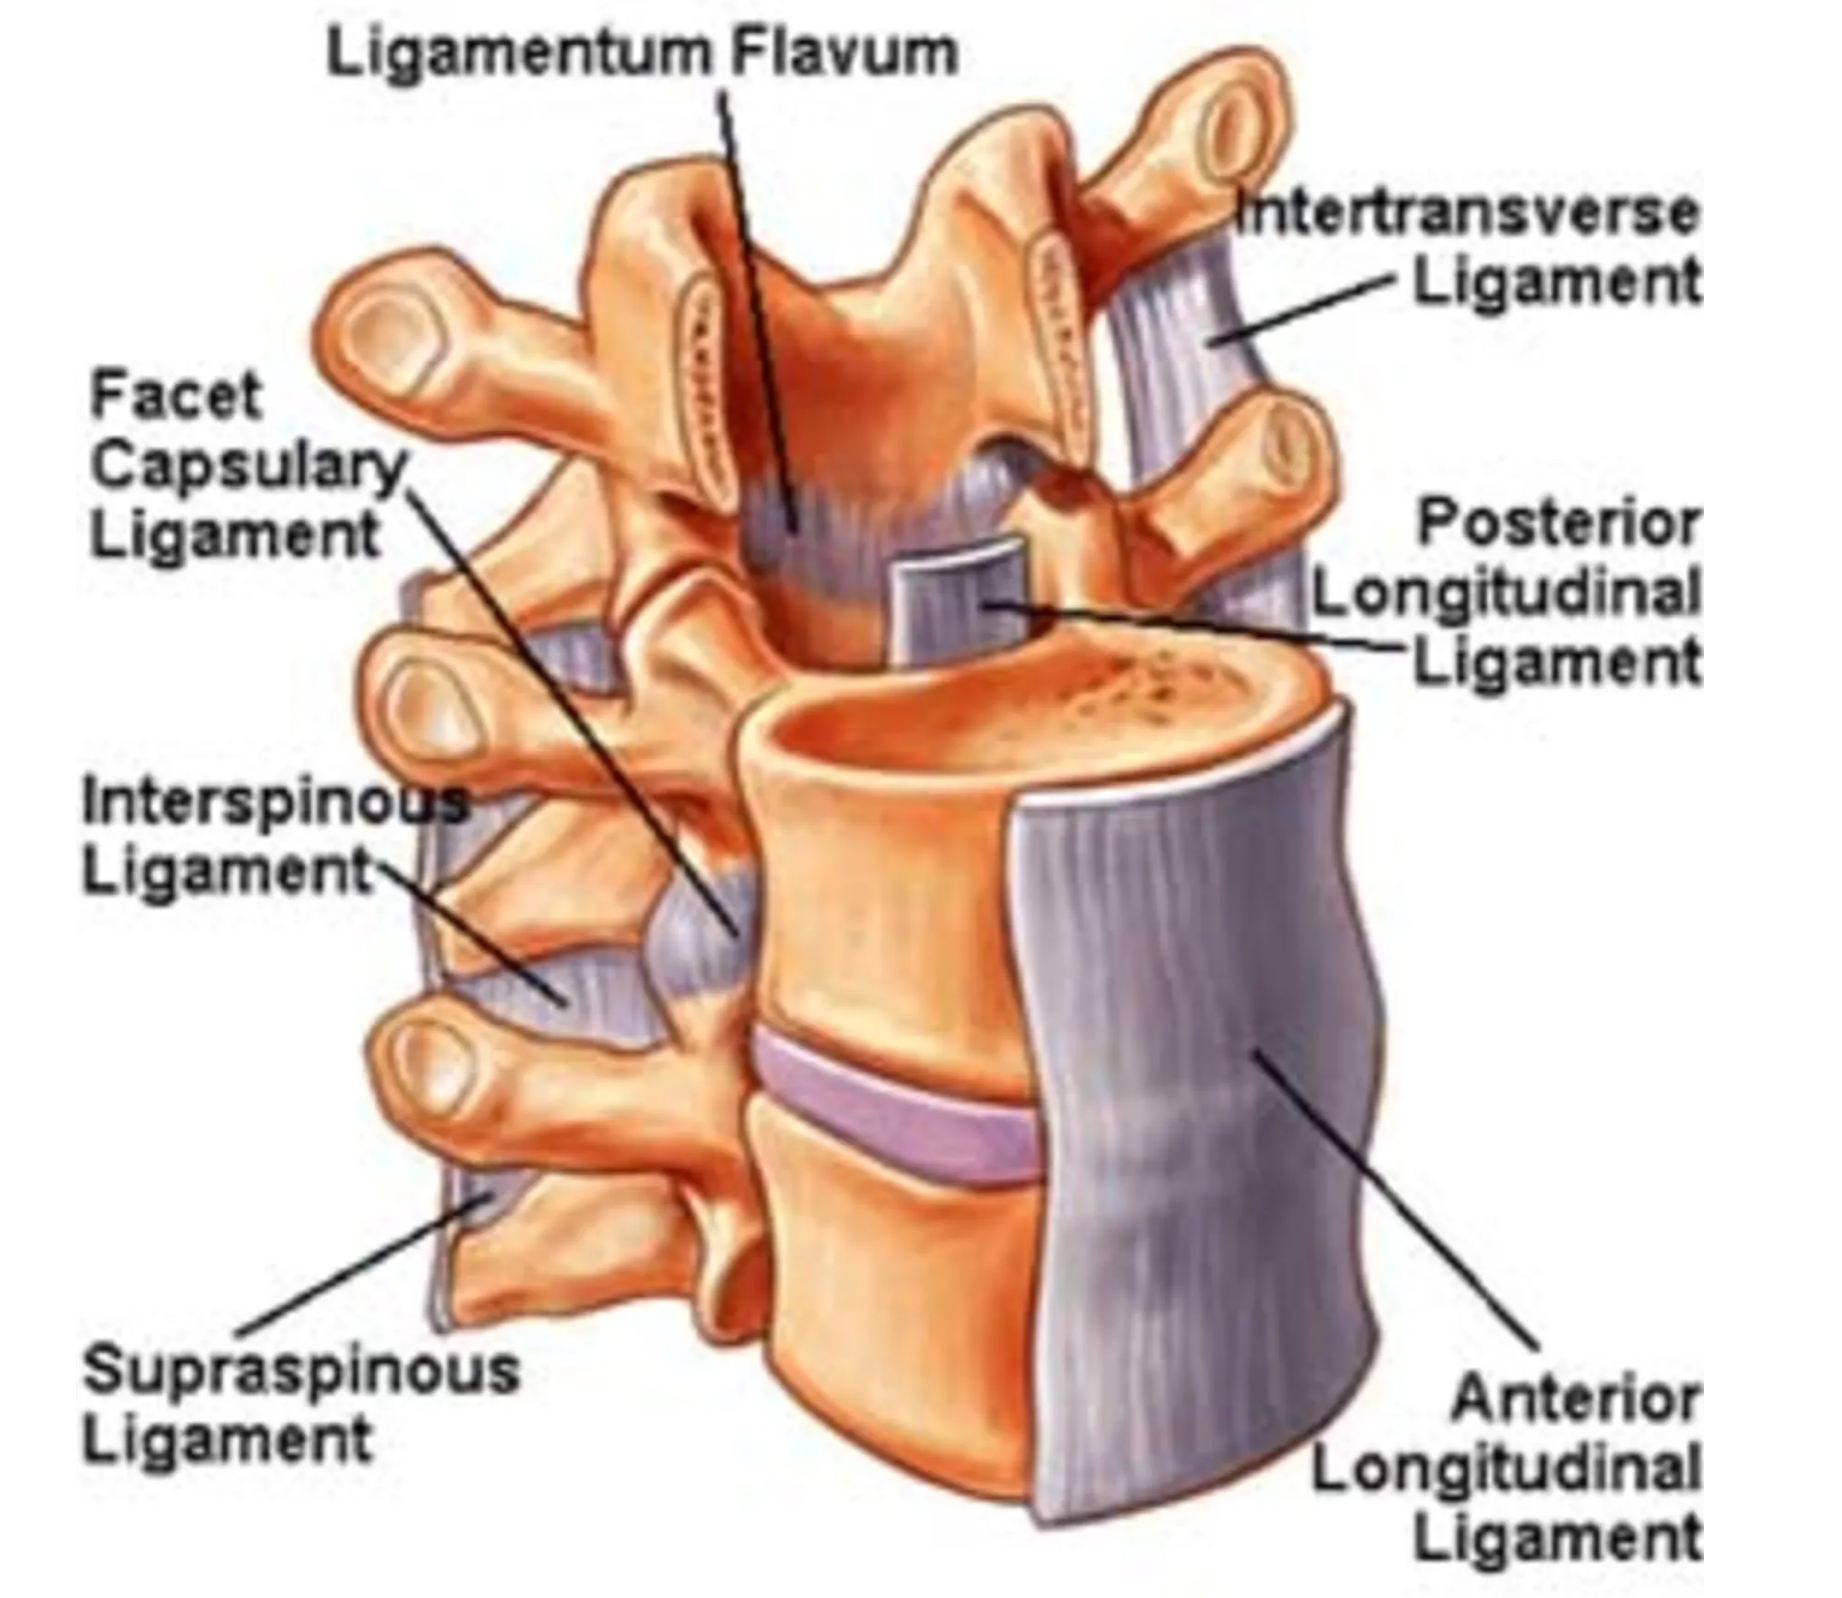

Posterior & Anterior Longitudinal Ligaments

Ligamentum Flavum

Interspinous Ligaments